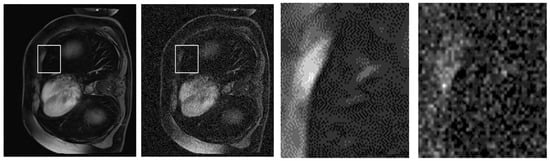

To further substantiate the quantitative improvements achieved by our proposed NLE-ANSNet method, we provide a comparative visual analysis in Figure 13. While the SSIM and PSNR validate the denoizing efficacy numerically, they do not always capture the perceptual quality and diagnostic reliability of the restored images. Excessive smoothing, for example, can artificially inflate these metrics while simultaneously compromising fine anatomical details. Hence, a qualitative assessment is necessary to illustrate the model’s ability to suppress noise while preserving clinically relevant structures.

Figure 13.

A qualitative comparison of CE-MRI denoizing results: (a) Ground truth image; (b) Noisy image with significant artifacts; (c) Output from a conventional denoizing method showing oversmoothing; (d) Output from the proposed NLE-ANSNet preserving fine anatomical details.